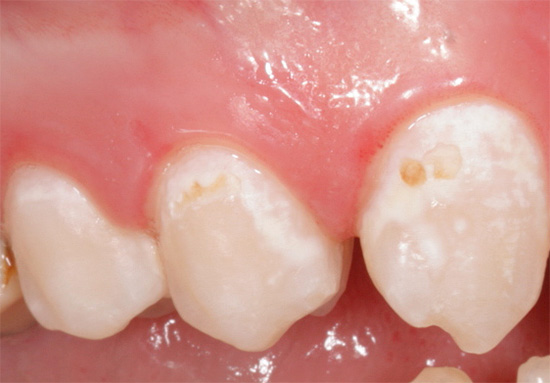

Pertanto, a proposito, è così importante vedere un dentista durante la gravidanza - se la carie viene rilevata nelle primissime fasi del suo sviluppo, il trattamento può essere effettuato utilizzando metodi di remineralizzazione senza anestesia, senza trapano e sensazioni spiacevoli. Ma la carie già lanciata senza anestesia guarirà davvero.

Di norma, il trattamento della carie secondaria durante la gravidanza, specialmente se la patologia procede in forma cronica, i dentisti preferiscono non condurre fino all'inizio del secondo trimestre. È nelle prime 12-13 settimane che vengono posati tutti i sistemi di organi del feto e il rischio di effetti negativi dei farmaci su questo periodo è massimo, anche se è ancora piccolo. A partire da 14-15 settimane, l'uso di anestetici speciali consente di eseguire la riabilitazione in sicurezza.

Prevenzione della carie e preparazione adeguata per la gravidanza

La prevenzione della carie nelle donne in gravidanza dovrebbe iniziare prima dell'inizio della gravidanza. Nella fase di pianificazione, la futura mamma dovrebbe essere controllata dal dentista, guarire tutti i denti malati, rimuovere la placca e il tartaro. A quel tempo, il medico elaborerà un programma di visite preventive che dovranno essere osservate (non è noto quale sarà la situazione cariogena in bocca con l'inizio della gravidanza e lo sviluppo fetale).